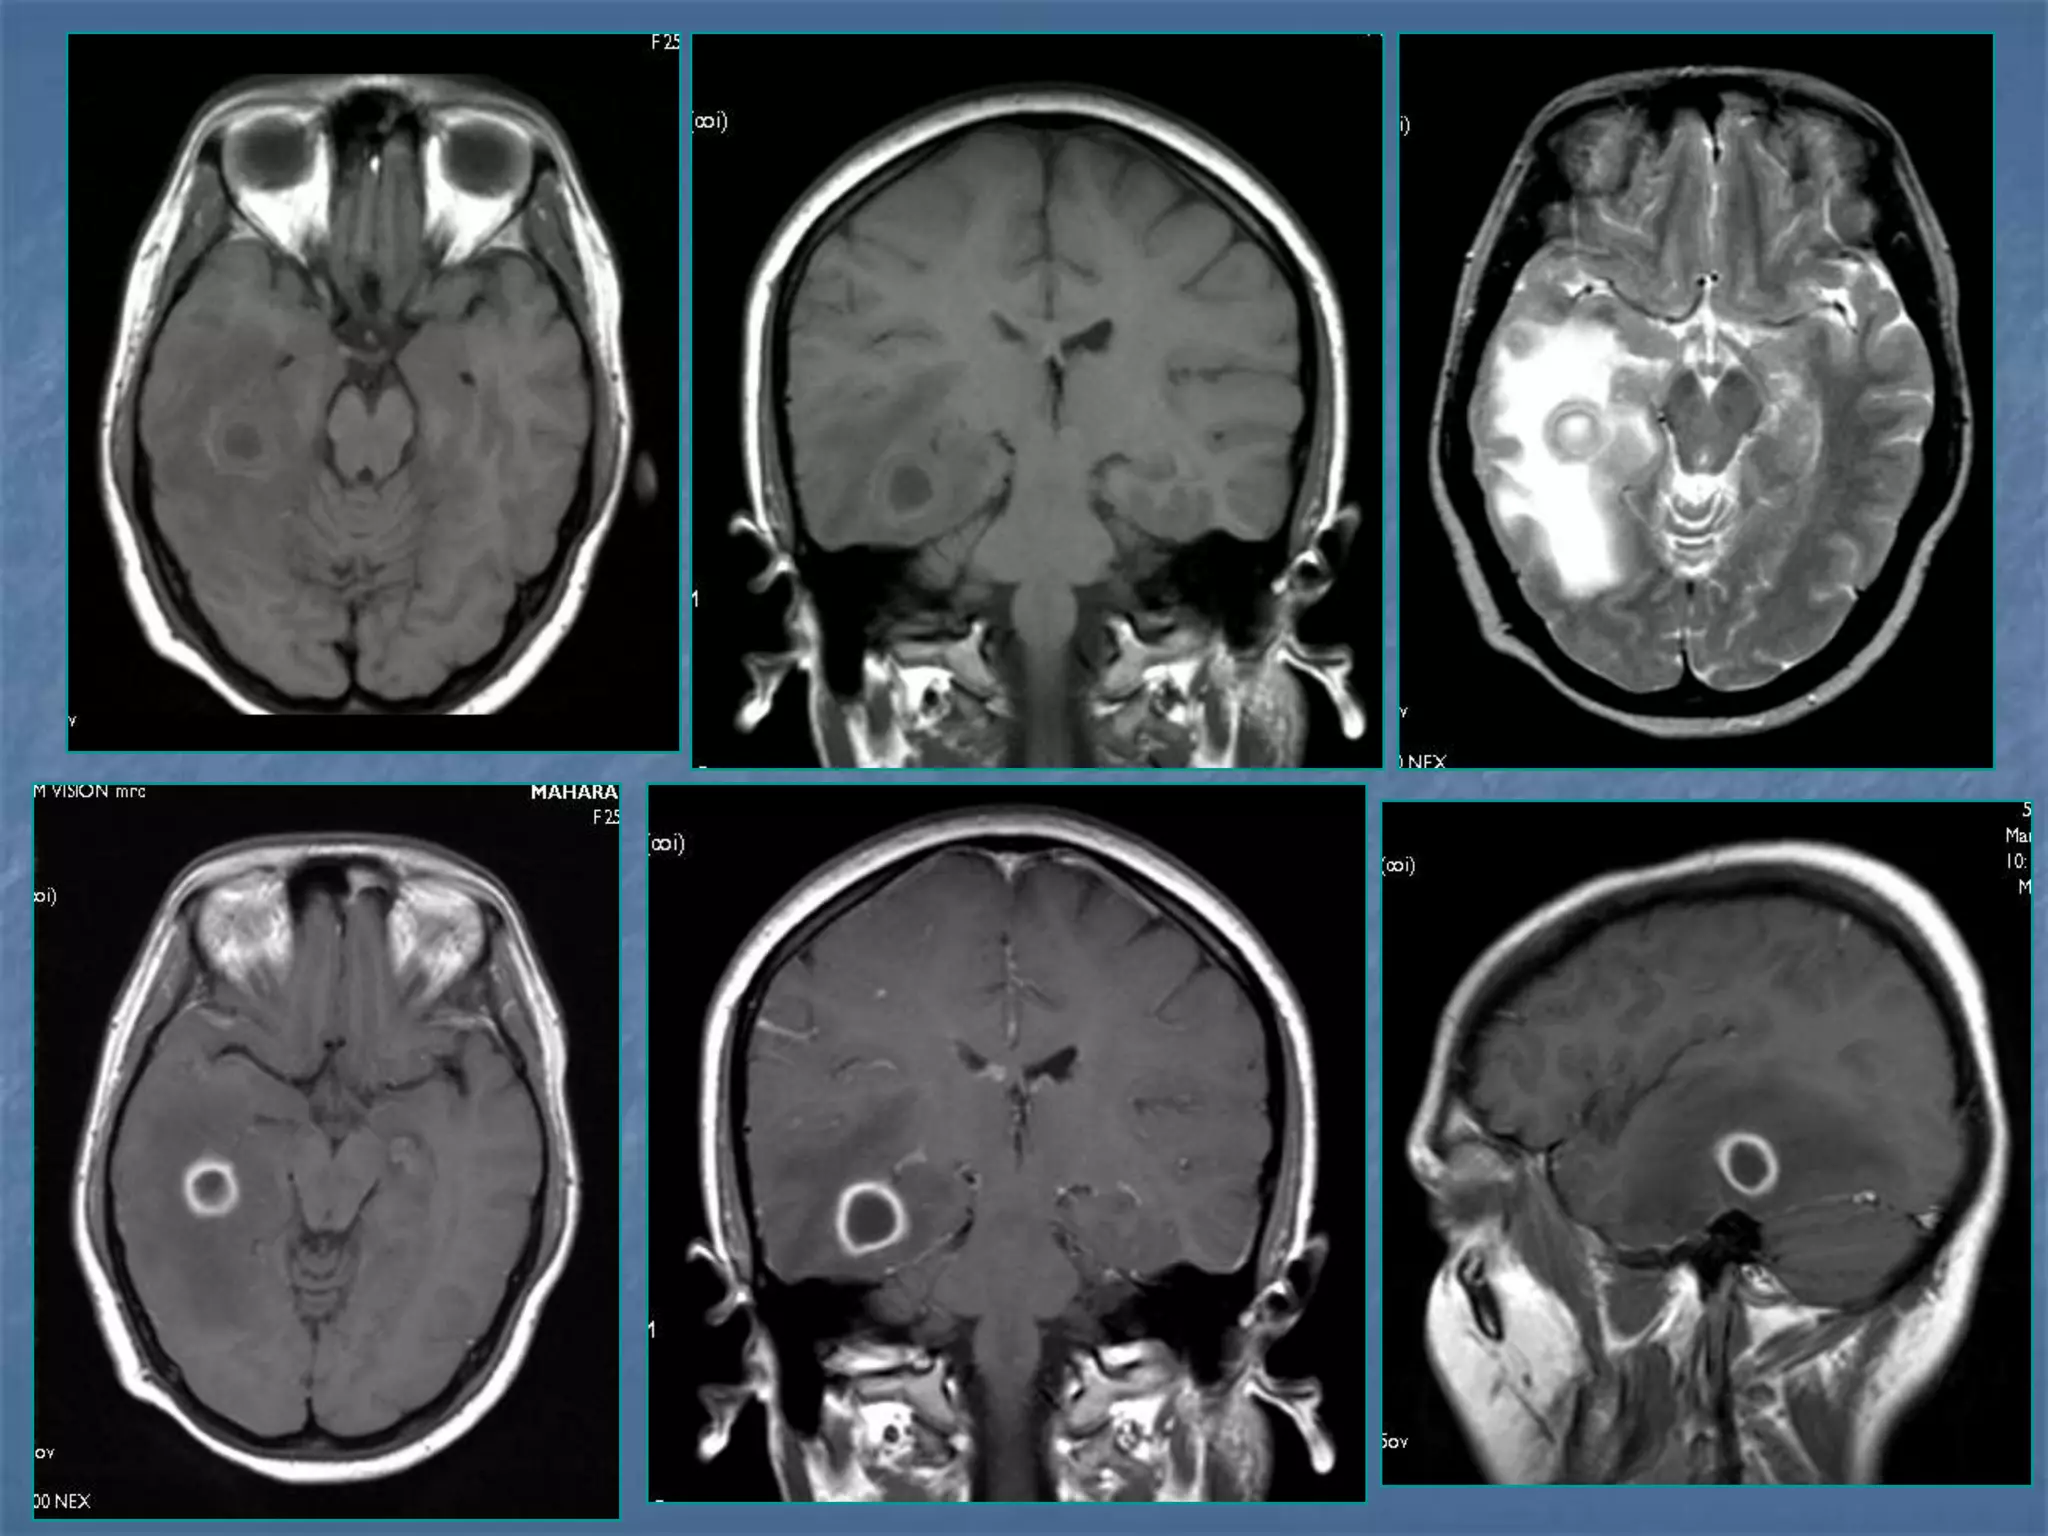

23 yr old male c/o fever and intense headache

 Ring enhancing lesions – granuloma /

abscess

 Calcifications

 Cerebritis

 Meningeal abnormalities

 Complications

Differential Diagnosis of Ring

Enhancing Lesions

 Granulomas

 Brain abscess

 Tumors – metastasis,

glioma

 Resolving hematoma

25 yr old lady c/o fever and altered sensorium x 1

wk. Had 1 episode of GTC seizures. Admitted

elsewhere , LP done showed proteins-55 mg % and

sugar –105 mg % ..

ABG- pH – 7.55

HCO3 – 28.3 , PCO2-32.9, PO2 –322.9,SPO2-99.8

CT – Normal

Discharged at request.

H/o fever,headache and vomitting on and off x 5

mths -

 O/E – GCS – E1V1M5

BP – 140/100 , PR – 116

Pupils – 4mm dilated , sluggish light reaction

Neck Rigidity +

Kernig’s & Brudeski’s - ve

 Hb-13.5

 TC- 12,200

 Platelets-4.2

 MP/MF – negative

 BUN, creatinine – normal

 Urine R/E – proteins +++, pus cells 5-8

 Coagulation Profile - WNL

 134/3.4/26/102